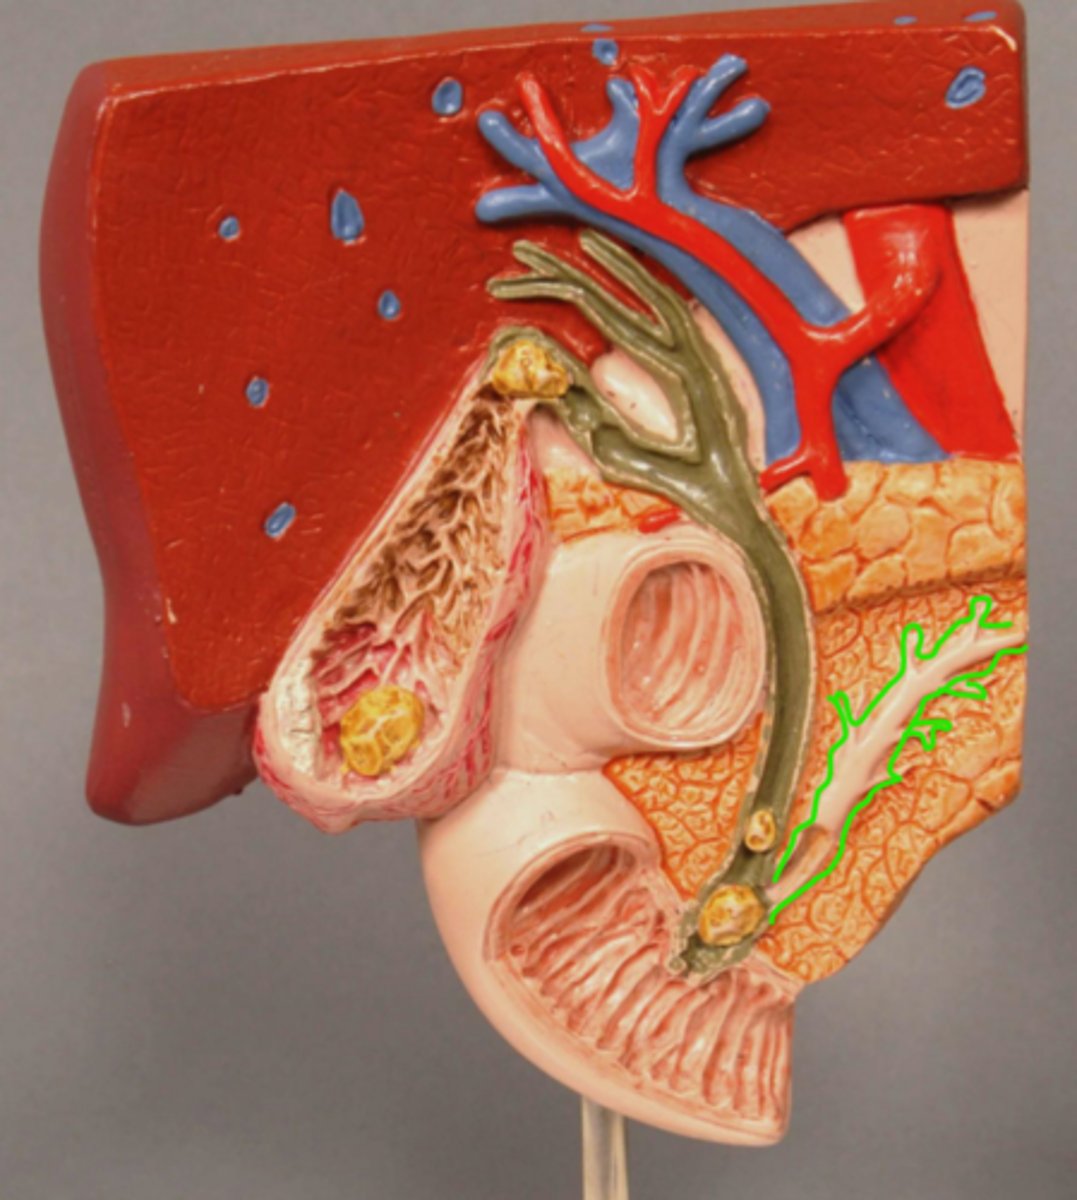

Pancreas

Pancreatic Duct